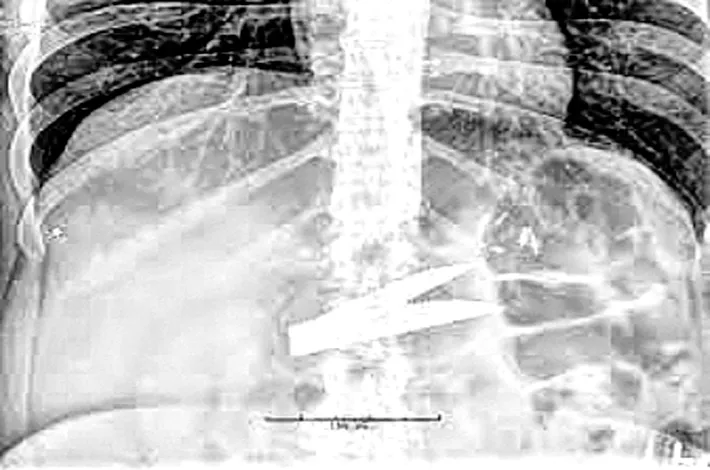

Surgical blade found inside patient’s body

Palnadu: A shocking incident of alleged medical negligence occurred at the Narasaraopet Government Hospital in Palnadu district. A 22-year-old patient, Rama Devi, was discovered to have a surgical blade left inside her body following an operation performed by Dr. Narayana Swamy and his team. Despite Rama Devi reporting severe post-operative pain, doctors initially dismissed her complaints as typical recovery symptoms. However, a scan conducted later confirmed the presence of the blade lodged near her thigh. The patient's family was horrified by the discovery and immediately staged a protest, demanding accountability and justice for the alarming lapse in care.